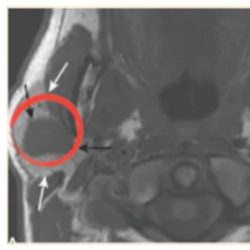

Fig. 3

‘Parotid pleomorphic adenoma’ detected in T1CE (right) instead of T1 (left).

1). This innovative approach has the potential to yield substantial benefits, including cost savings, time efficiency, and reduced patient discomfort, by eliminating the necessity for multiple MRI scans that require patients to remain motionless for prolonged periods. Moreover, taking the same anatomical structure in a different pulse sequence can assist diagnosticians in detecting underlying pathologies or injuries, such as brain tumours or oedema, as illustrated in Figs.

2,

3, and

4.